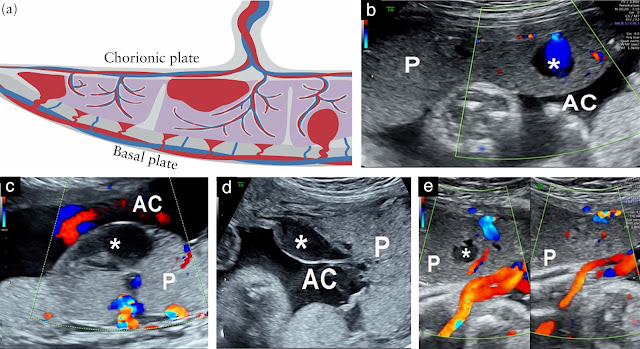

Hình 1

(a) Sơ đồ minh họa các vị trí thường gặp của hồ huyết trong nhau thai: hồ huyết rìa, hồ huyết dưới màng đệm và hồ huyết trung tâm thùy.

(b–e) Hình ảnh siêu âm dọc qua bụng của bánh nhau (P) trong các thai kỳ không biến chứng, cho thấy:

(b) Hồ huyết trung tâm thùy ở tuổi thai 32 tuần;

(c) Hồ huyết dưới màng đệm có mạch cấp máu tương ứng ở 22 tuần;

(d) Hồ huyết rìa ở 20 tuần;

(e) Hồ huyết trung tâm thùy ở 34 tuần, trước (trái) và sau (phải) khi ấn nhẹ đầu dò.

AC: khoang ối.